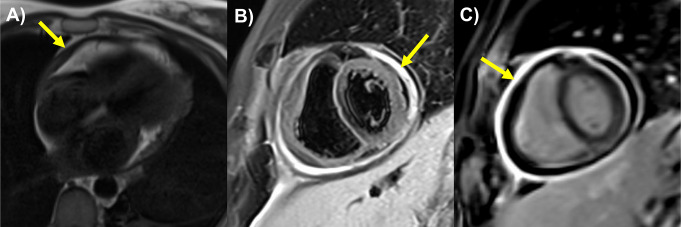

Recent findings: Multi-modality cardiac imaging is the cornerstone to the evaluation and treatment of pericardial diseases. The addition of Interleukin (IL-1) blockers or biologics (Rilonacept, Anakinra) in the last few years provides targeted therapy for these patients. Using imaging guided therapy (IGT) these complex patients require close, continuous follow up and monitoring as well as frequent medication titration. The outcomes for these pericardial patients are improved with these centers due to the specialized medical and surgical care. Advanced Practice Providers play a vital role in a pericardial center with ordering the appropriate imaging and labs, handling medication titration, and providing patient education and continuity of care for these patients. They have been shown to decrease mortality, increase quality of care, and increase medication adherence.